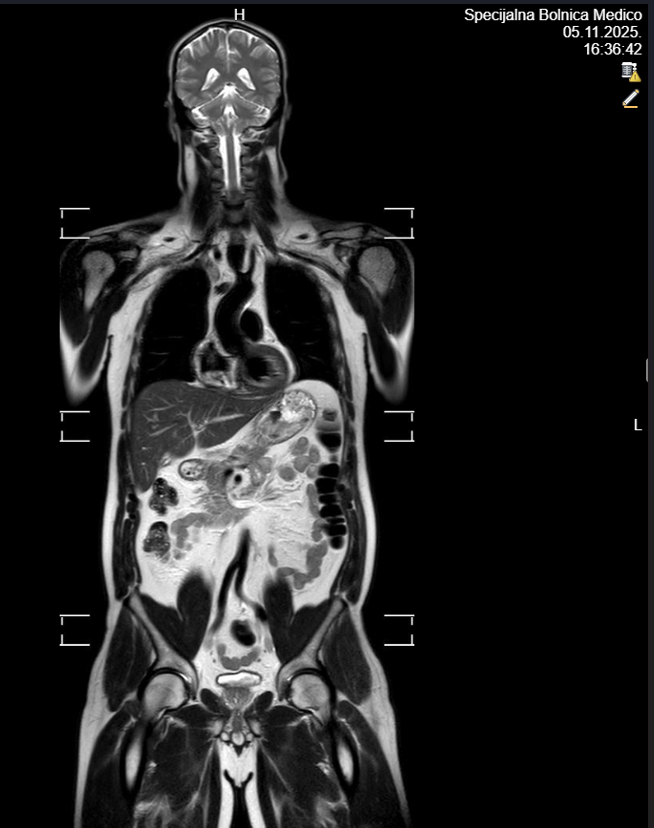

Specijalna bolnica Medico predstavila novu uslugu – magnetsku rezonancu cijelog tijela: bezbolnu, neinvazivnu pretragu za preventivnu procjenu zdravlja cijelog organizma

RIJEKA Magnetska rezonanca cijelog tijela, poznata kao MR cijelog tijela, sve češće se koristi u modernoj medicini zbog svoje neinvazivnosti i preciznosti. Radi se o bezbolnoj radiološkoj pretrazi koja omogućuje uvid u strukture čitavog organizma tijekom jednog snimanja, bez izlaganja pacijenta ionizirajućem zračenju. Ova metoda smatra se vrlo sigurnom te je najčešće namijenjena osobama s povećanim rizikom za razvoj zloćudnih bolesti, ali i onima koji žele preventivno provjeriti svoje zdravstveno stanje. Osim za ranu detekciju tumora i upalnih procesa, MR cijelog tijela često služi kao dopuna drugim radiološkim pregledima.Snimanje se izvodi u trajanju od oko 40 minuta, dok cijeli proces prosječno traje sat vremena. Pregled se obavlja bez korištenja kontrastnog sredstva i bez zračenja, a za pacijente s izraženom nelagodom u skučenom prostoru moguće je snimanje uz kratkotrajnu sedaciju.

U sklopu jednog snimanja, MR omogućuje prikaz mozga, struktura prsnoga koša, trbušnih organa poput jetre, žučnog mjehura, gušterače, slezene i bubrega, zatim nadbubrežnih žlijezda, zdjeličnih organa (mokraćni mjehur, rektum, maternica i jajnici kod žena te prostata kod muškaraca), kao i cijelu kralježnicu – vratnu, prsnu i lumbalnu. Pregled pruža orijentacijski uvid u stanje organizma i može otkriti eventualne promjene koje zahtijevaju dodatnu obradu. Nakon pregleda pacijent dobiva preporuke za daljnju dijagnostiku i eventualne terapijske postupke, čime se olakšava pravovremeno donošenje odluka o zdravstvenoj skrbi.